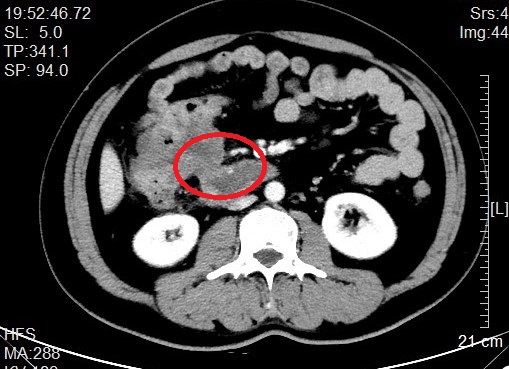

来自省内正值中年的邹先生和张先生都因“阵发性腹痛不适感”就医而发现结肠肿瘤,慕名转诊找到我院治疗。杨春康教授接诊,经过详细全面的检查后,发现二者的病情相似,都为升结肠近肝曲部的肿瘤且肿瘤已侵犯临近的重要脏器——十二指肠,全身其他部位没有发现肿瘤转移病灶,属于局部晚期病例。面对仍有治愈希望的病人以及家属的殷切希望,尽管病情高度复杂,手术风险和压力巨大,杨春康教授和他率领的医疗护理团队没有在困难面前退缩。在与病人及家属充分沟通后,决定为他们手术,并制定周密的手术方案。

虽然已有过多例成功案例在先,但面对此高难度手术,杨春康教授始终严阵以待,在总结前期手术经验基础上,与麻醉科、手术室护理团队等做好充分的术前准备,在团队成员的密切配合下,历时5小时余,顺利完整切除肿瘤,成功完成手术,术中出血近约300ml。